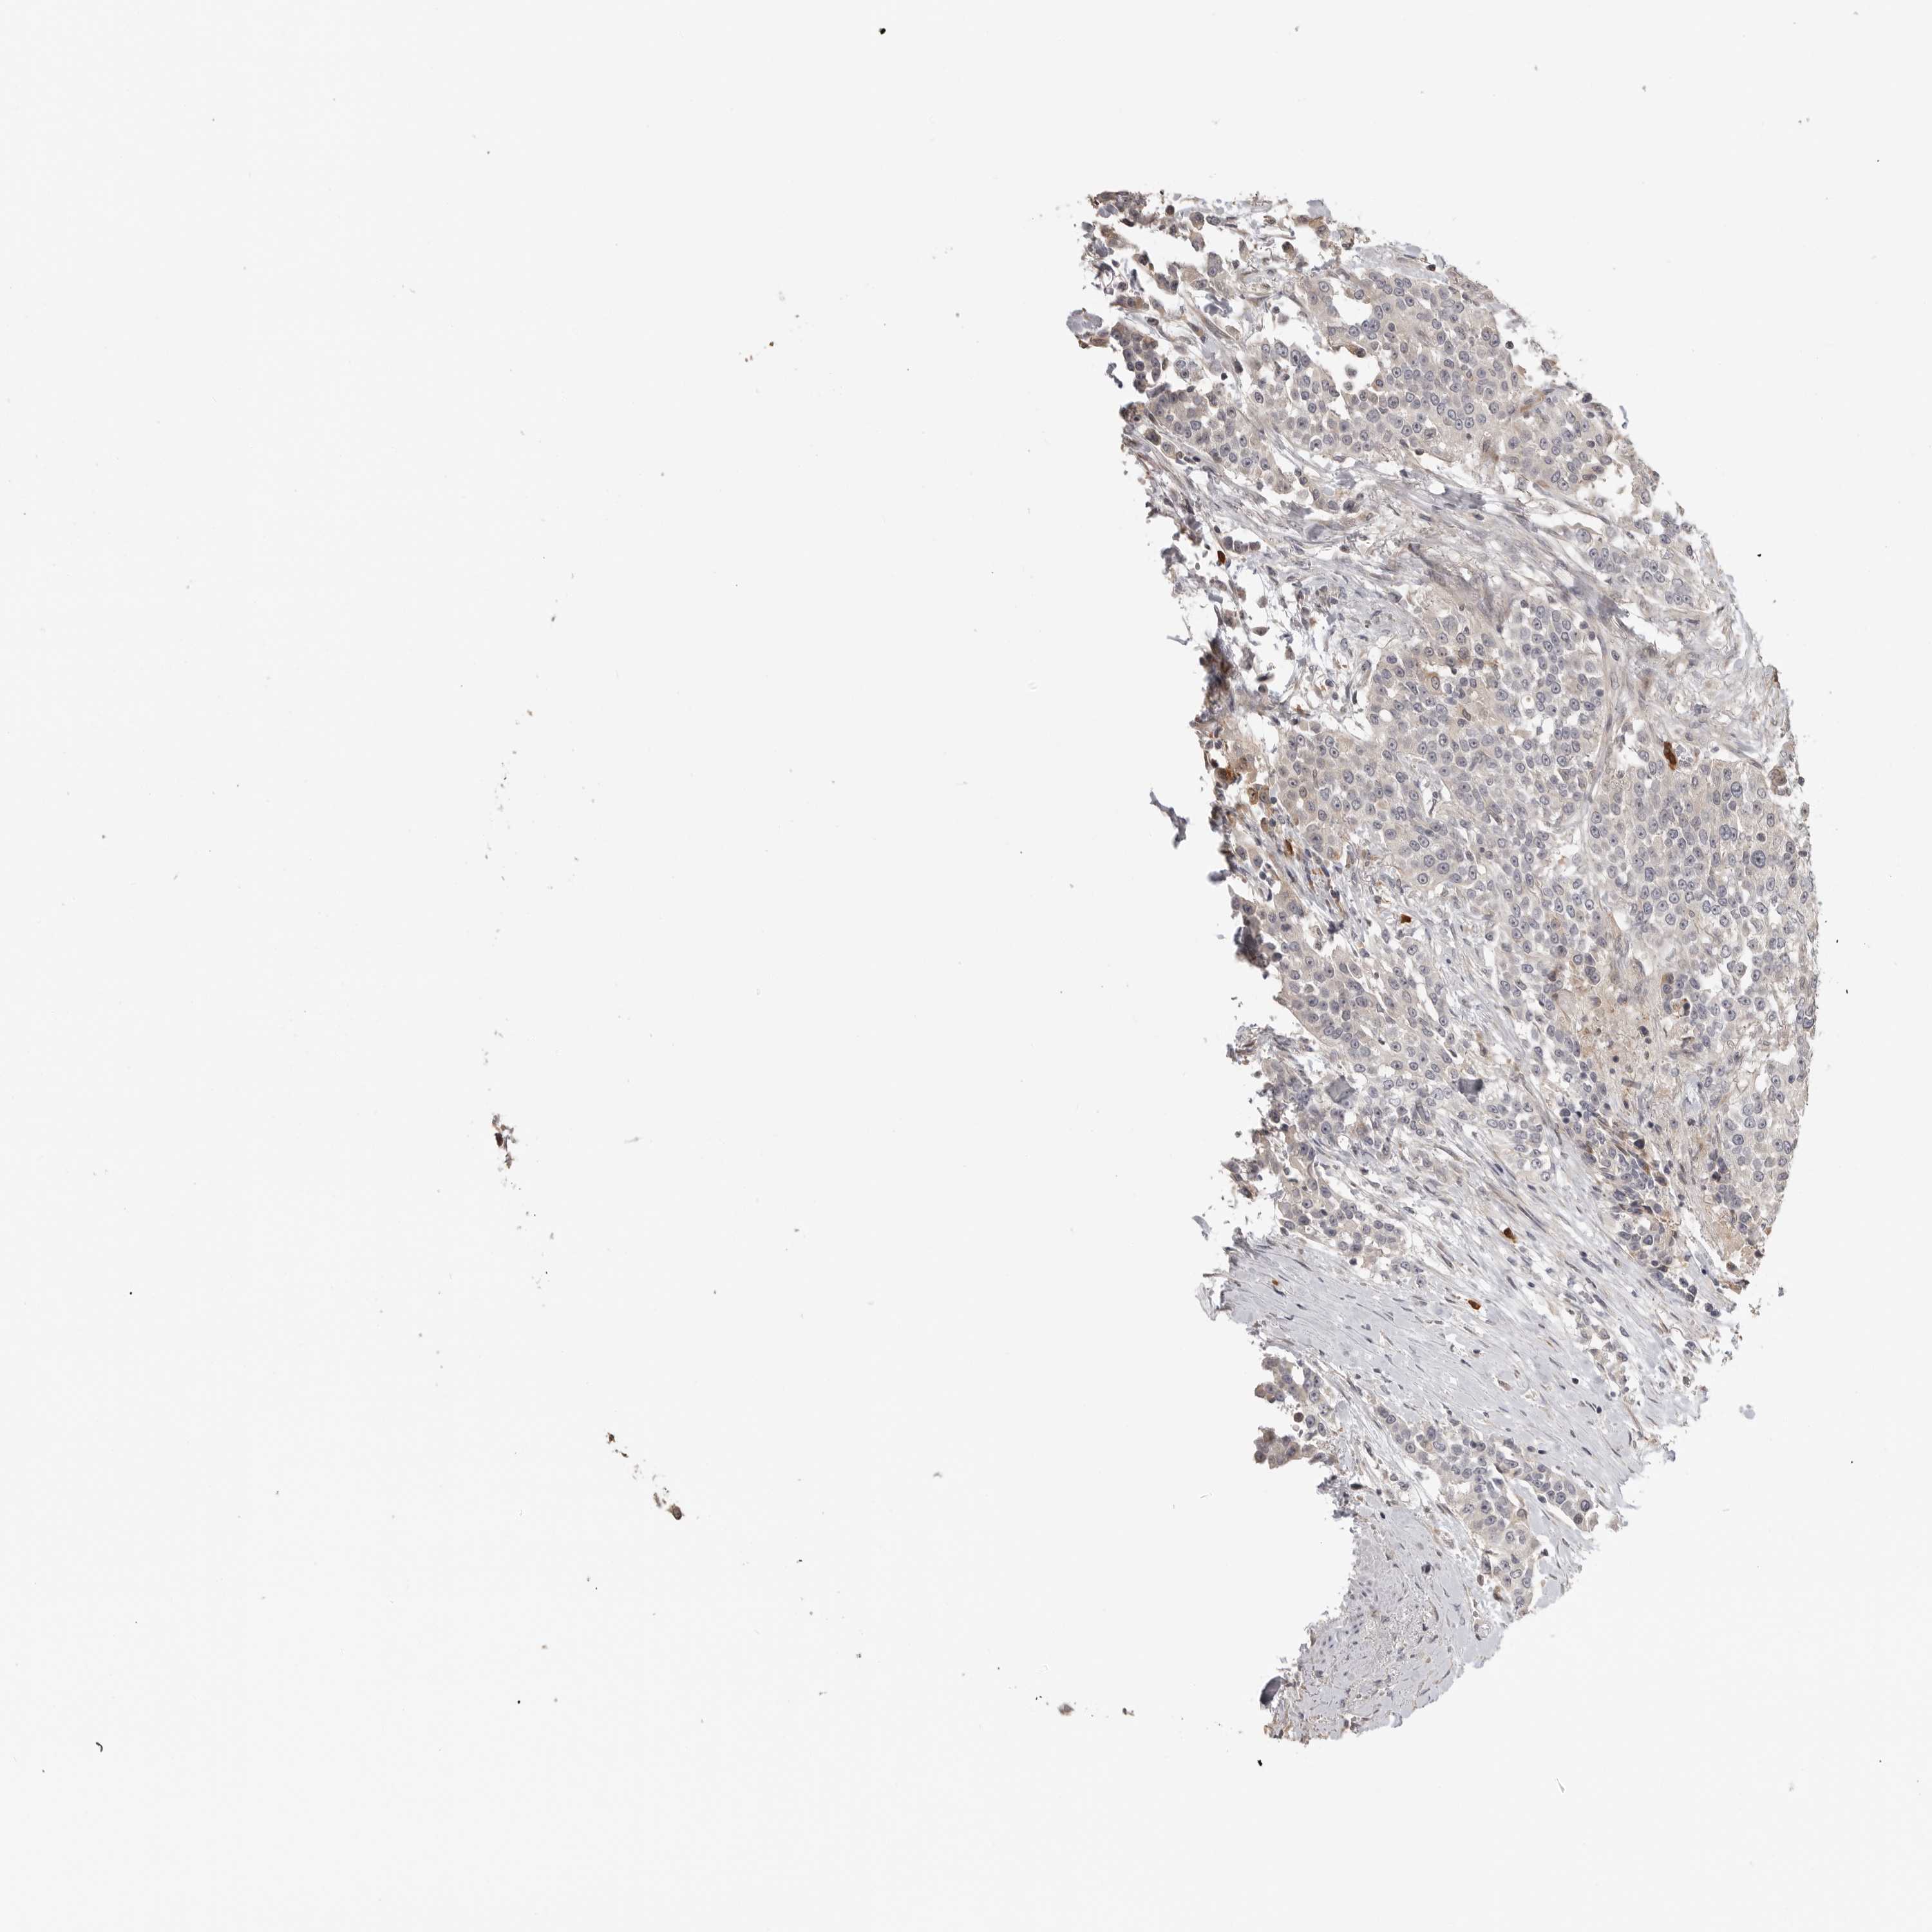

UROTHELIAL CANCER - Protein expressioni

A mouse-over function shows sample information and annotation data. Click on an image to view it in a full screen mode. Samples can be filtered based on level of antibody staining by selecting one or several of the following categories: high, medium, low and not detected. The assay and annotation is described here.

Note that samples used for immunohistochemistry by the Human Protein Atlas do not correspond to samples in the TCGA dataset.

Antibody stainingi

Antibody staining in the annotated cell types in the current human tissue is reported as not detected, low, medium, or high, based on conventional immunohistochemistry profiling in selected tissues. This score is based on the combination of the staining intensity and fraction of stained cells.

Each image is clickable and will lead to virtual microscopy that enables deeper exploration of all samples and also displays staining intensity scores, fraction scores and subcellular localization as well as patient and tissue information for each sample.

Antibody CAB072820

Urothelial carcinoma, Low grade

Urothelial carcinoma, High grade